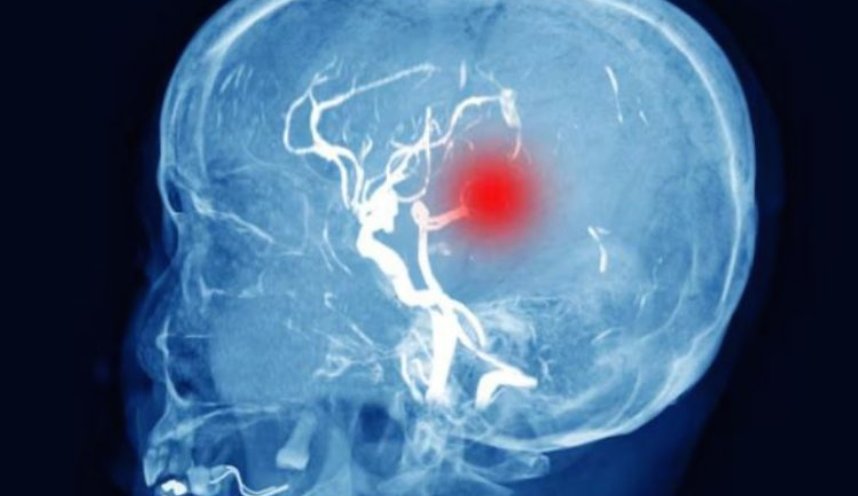

ट्रॉमेटिक ब्रेन इंजरी (टीबीआई) यानी सिर की गंभीर चोट के बाद ठीक हो रहे मरीजों के लिए काशी हिंदू विश्वविद्यालय में चिकित्सा विज्ञान संस्थान में महत्वपूर्ण शोध हुआ है । रक्त में मौजूद विशेष सूजन संबंधी संकेतों के जरिये यह पहले ही पता लगाया जा सकता है कि मरीज को भविष्य में पोस्टमैटिक हाइड्रोसिफलस (दिमाग में पानी भरने की समस्या) होने का कितना खतरा है। सिर की चोट के बाद कई बार मरीजों के मस्तिष्क में तरल पदार्थ (सीएसएफ) जमा होने लगता है, जिसे हाइड्रोसिफलस कहते हैं इसका समय पर निदान करना डाक्टरों के लिए हमेशा चुनौती रहा है।

बीएचयू के न्यूरो सर्जरी विभाग में ब्रेन इंजरी के बाद मरीज की सीटी स्कैन रिपोर्ट। इसमें दिमाग में भरा पानी (काले रंग में) देखा जा सकता है।